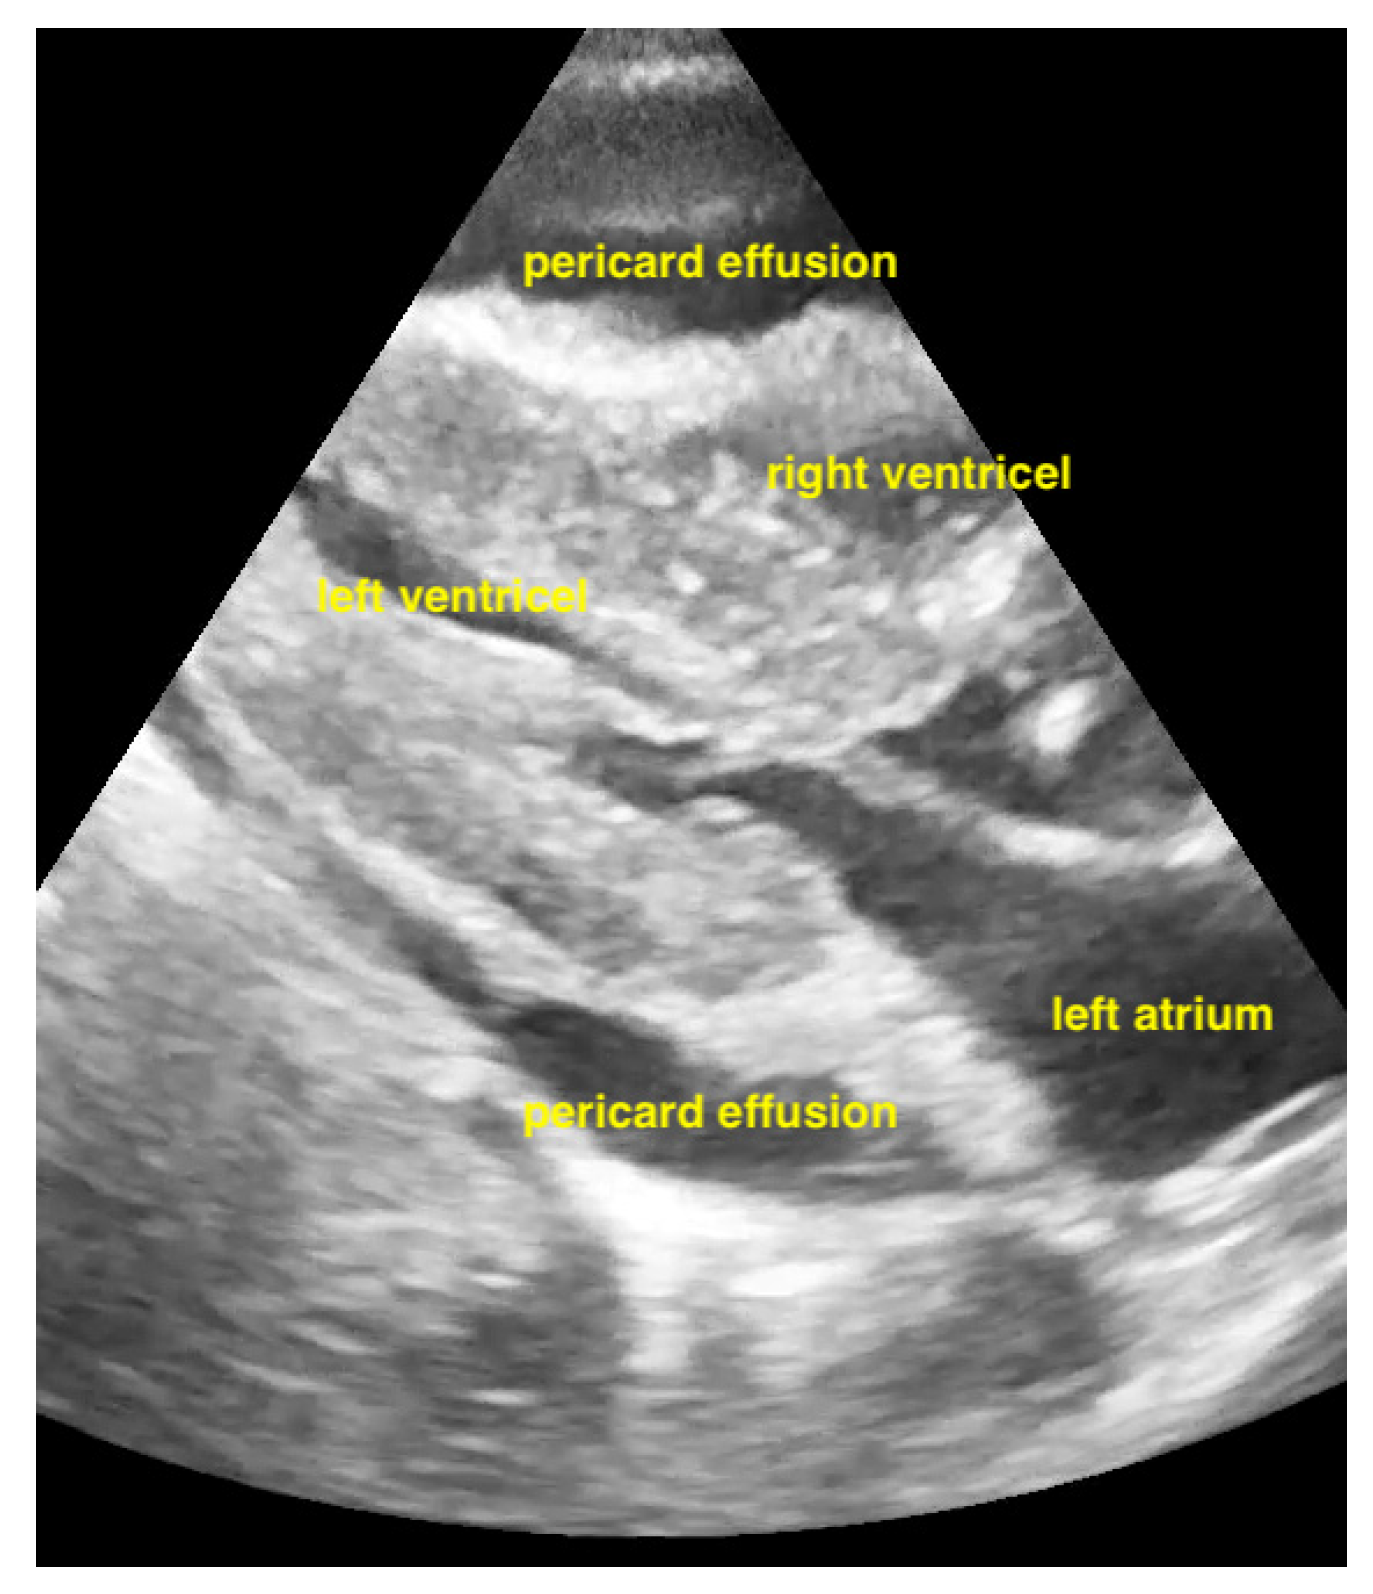

Figure 10.

Pericardial effusion in subxiphoidal view compresses the right ventricle.